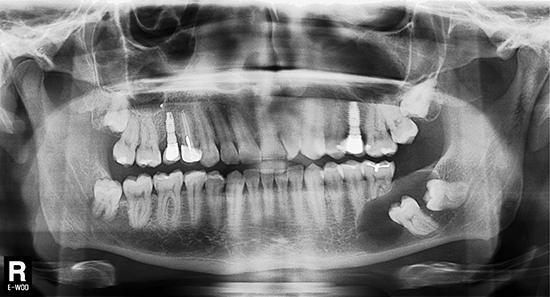

Tras realizar la evaluación radiológica bidimensional, en la ortopantomografía (Planmeca ProMax 3D Classic, Helsinki, Finland) se observó una imagen osteolítica radiotransparente que englobaba a los dientes 3.7 y 3.8 no erupcionados. Además la lesión había producido rizólisis de los dientes 3.5 y 3.6. El paciente era portador de prótesis implantosoportada a nivel 1.5 y 2.5, y había recibido tratamiento de conductos en el diente 1.4. Se observó la presencia de los cordales no erupcionados en el primer, segundo y cuarto cuadrante (Fig. 2).

Figura 2. Evaluación radiológica bidimensional. La ortopantomografía advierte la presencia de un proceso osteolítico circunscrito a las coronas de los dientes 3.6 y 3.7 no erupcionados. Nótese la reabsorción radicular de los dientes 3.5 y 3.6 debido a la extensión del proceso osteolítico en sentido antero posterior.

La TCHC (Planmeca ProMax 3D Classic) mostró una extensa imagen osteolítica poco radiodensa en el tercer cuadrante. La lesión era visible en los planos axial, coronal y sagital. Se observó la afectación de la cortical vestibular relacionada a la lesión osteolítica (Fig. 3).